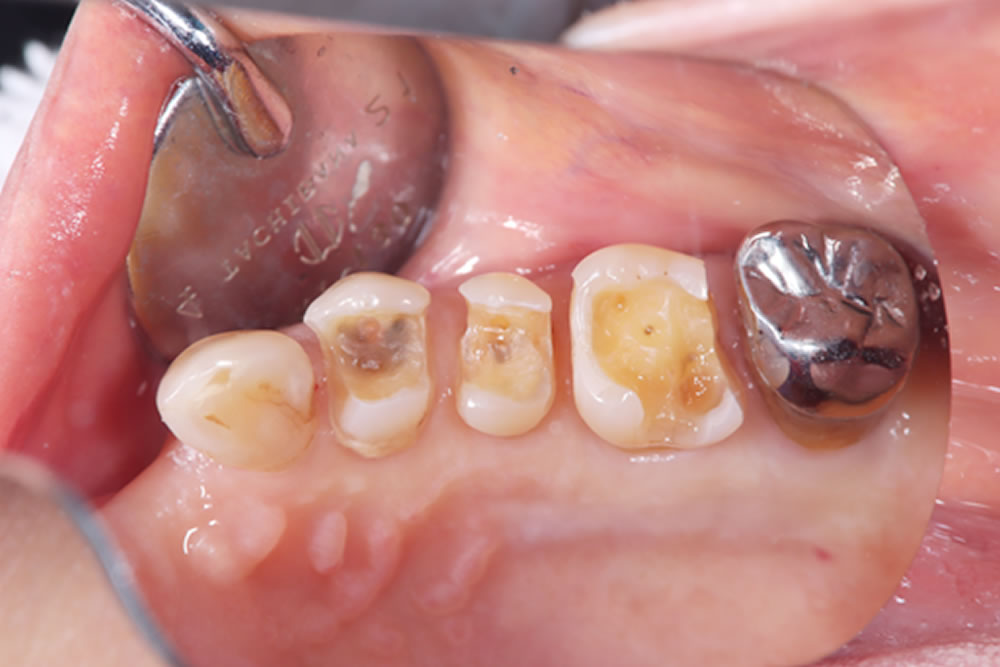

メタルインレーの除去

当該歯のメタルインレーを除去したところ、歯の内部に2次カリエス(虫歯の再発)を認めました。

う蝕検知液(虫歯部分に着色する薬液)を使用しながら、慎重に虫歯除去を行ったところ、遠心に歯根破折を確認しました。歯周ポケットが深かった部位と破折線が一致しており、このままつめ物を装着しても予後不良となる可能性があることを患者さまに説明したところ、抜歯とインプラントによる治療を希望されました。

また、他の銀歯の下にも複数の二次カリエスが認められたため、患者さまは口腔内全体の銀歯を除去し、再治療を行うことを希望されました。